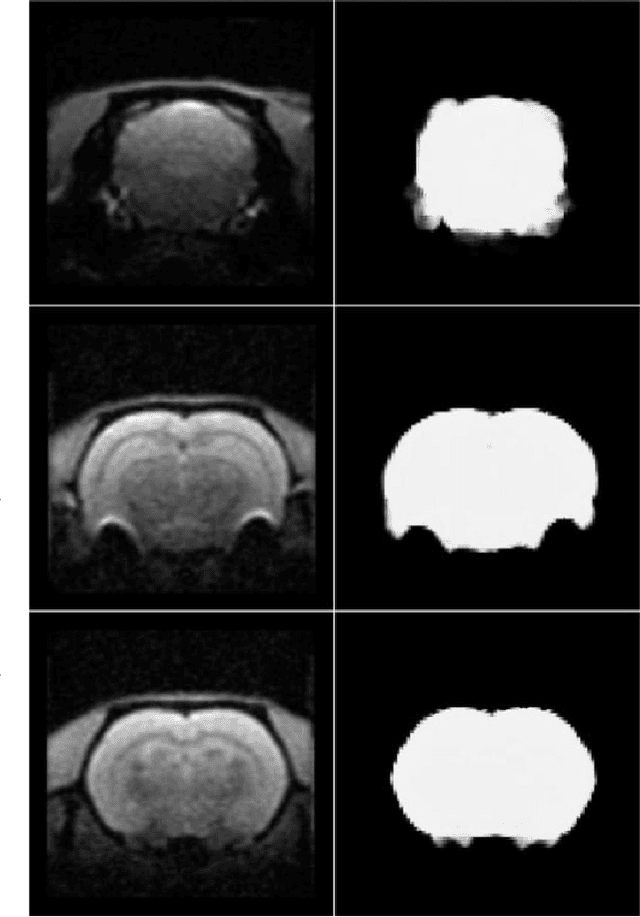

Removing skull artifacts from functional magnetic images (fMRI) is a well understood and frequently encountered problem. Because the fMRI field has grown mostly due to human studies, many new tools were developed to handle human data. Nonetheless, these tools are not equally useful to handle the data derived from animal studies, especially from rodents. This represents a major problem to the field because rodent studies generate larger datasets from larger populations, which implies that preprocessing these images manually to remove the skull becomes a bottleneck in the data analysis pipeline. In this study, we address this problem by implementing a neural network based method that uses a U-Net architecture to segment the brain area into a mask and removing the skull and other tissues from the image. We demonstrate several strategies to speed up the process of generating the training dataset using watershedding and several strategies for data augmentation that allowed to train faster the U-Net to perform the segmentation. Finally, we deployed the trained network freely available.